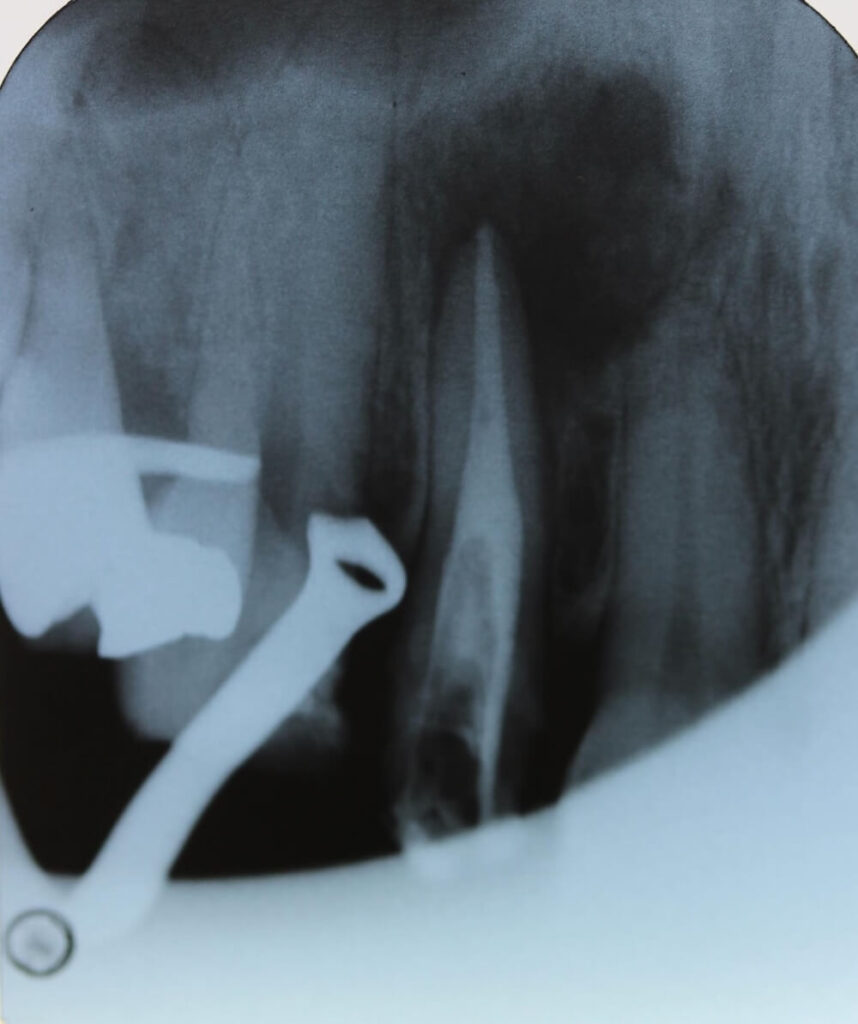

治療はすべて ラバーダム防湿(お口の細菌が歯の中に入らないようにするゴムのシート)を行った上でスタートしました。

その日のうちに根管(神経のあった場所)の消毒ができたため、

当日中に根管充填(薬を詰める処置) まで完了しました。

根の先の形態は、これまでに何度も治療が繰り返されていた影響で 大きく開いている状態(拡大・変形) でした。

そのため、治癒が得られにくい可能性や、必要に応じて 外科的歯内療法(歯根端切除術)へ移行する可能性がある ことを、事前に患者さんへ丁寧にご説明しました。